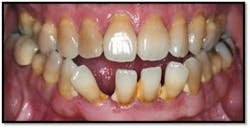

Generalized 4-5mm pockets with BOP

UL/LL reflected in a mirror and UL/LL radiograph